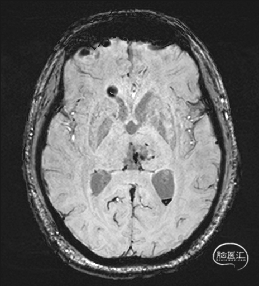

术前MRI检查

术前DTI检查

根据MRI及DTI显示,只有在丘脑与上丘之间的点(dot)进入病变才可能在切除病变时最大程度保护神经功能,由于上述原因,该“点”在术中显露极其困难,虽有导航指引,电生理监测的条件下,对术者的耐心、技术、经验及体能依然是极大的挑战;

术前详细的磁共振检查,包括平扫增强,SWI及DTI,可以规划出手术最适宜的路径及切入点;